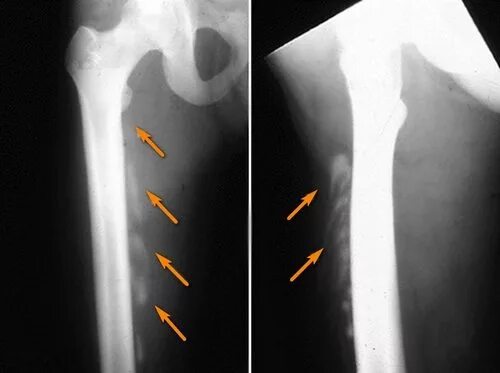

Оссифицированный миозит